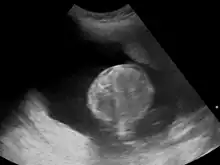

Polyhydramnios is a medical condition describing an excess of amniotic fluid in the amniotic sac. It is seen in about 1% of pregnancies.[1][2][3] It is typically diagnosed when the amniotic fluid index (AFI) is greater than 24 cm.[4][5] There are two clinical varieties of polyhydramnios: chronic polyhydramnios where excess amniotic fluid accumulates gradually, and acute polyhydramnios where excess amniotic fluid collects rapidly.